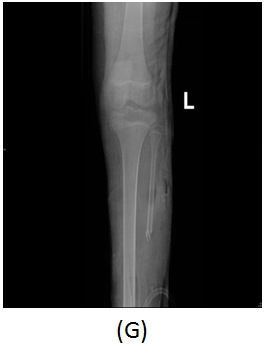

A girl, 11yearsold Saudi presented to us with progressive swelling of the left lower limb, localized above the left ankle with complaints of pain and limping gait. She had visited many clinics for her pain and swelling with no relief to her symptoms. The patient was examined clinically and there was a swelling in the lateral aspect of the distal leg tender firm too hard with intact skin over it, 4x3 cm, no other systemic clinical finding of note. X-ray of the left leg (Figure 1) showed aggressive lytic lesion of the distal fibula. Thence patient was investigated with basic lab works plus systemic and local staging for further diagnosis. She was admitted under us in pediatric surgical ward for open biopsy of the distal fibular lesion and CT of the lower limb (Figure 2) showed destructive bone lesion involving the distal end of the fibula associated with extensive destruction and aggressive periosteal reaction associated with large soft tissue mass 4.5 x 5 cm in maximum axial dimension. Also, MRI of the lower limb (Figure 3) showed there is a large destructive bone lesion involving the distal diaphysis of the left fibula. This lesion does not cross the growth plate. It is associated with aggressive periosteal reaction along with a large soft tissue mass that appears of high signal intensity in T2 and intermediate to low signal intensity in T1 sequences. This was followed by technetium-99m MDP scintigraphy (Figure 4), it showed an increased tracer uptake in the distal left fibula, extending to the left ankle and the left foot. Excisional biopsy was taken from the proximal and distal margin of the lesion in the left fibula which confirmed Ewing's Sarcoma. According to the histopathology department, they reported that there is no evidence of residual tumor i.e free resection margins. (Figure 5) The patient was referred from us to pediatric oncology clinic for further evaluation. She was electively admitted to the hospital for staging and central line insertion to start chemotherapy. She treated as per Ewing sarcoma protocol in our hospital. Patient was put on neoadjuvant chemotherapy which included vincristine, cyclophosphamide, doxorubicin and etoposide, and if osfamide 3 times weekly. After 6 months of chemotherapy, we recommend to her family to do a surgery. We did a wide surgical resection of the tumor in the left leg. Subcutaneous tissue was dissected and isolation of superficial peroneal nerve was done. Dissection of lateral compartment of the left leg up to 16cm proximal to the lateral malleolus and distally, until the distal physis (Figure 6). The tendons of the peroneus longus, peroneus brevis, and flexor halluces longus were sacrificed and the ruminants were used to reconstruct for the lateral aspect of the left ankle using suture anchors (Figure 7). K-wires were used to do temporary arthrodesis (Figure 8). The surgical wound was closed in layers. VAC dressing was also applied as standard care management in Oncology cases at KFMC and backs lab was applied (Figure 9). The last MRI done for the patient showed there is altered signal intensity of the soft tissue with post-contrast enhancement. However, the dimensions of this area of altered signal intensity are decreased as compared to previous MRI. There is no evidence of soft tissue mass lesion (Figure 10). According to the last patient's follow up after six months post-operation it shows no Valgus deviation, normal ankle motion, mobilizing full weight bearing with splint assistant during physical examination (Figure 11). Also, X-rays and MRI finding shows no residual mass lesion or local recurrence.

Figure 6 Interoperation images. Tumor in the distal end (A). Remnant of Prenous Longus Tendone (B). Isolation of the Superficial Peroneal Nerve (C). Resection of distal Fibula Tumor (D) Tumor resected with reservation of neurovascular pedicle (E). VAC dressing (F). AP view of plain X-ray of the left leg showed dissection of lateral compartment of the left leg during resection of the tumor (G).